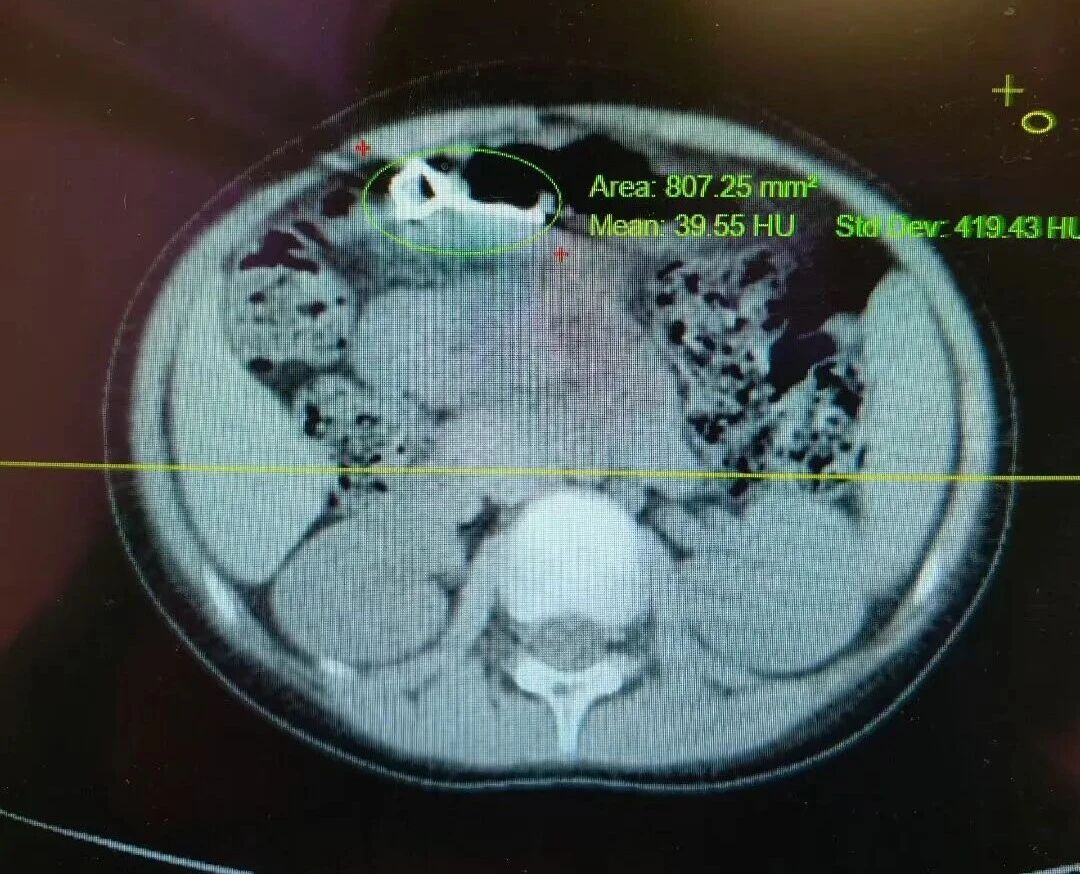

急诊科接诊后,迅速联系耳鼻喉科医师进行紧急检查,但发现异物已不在咽喉部。随后的CT检查明确显示:金属异物位于患者胃窦处。